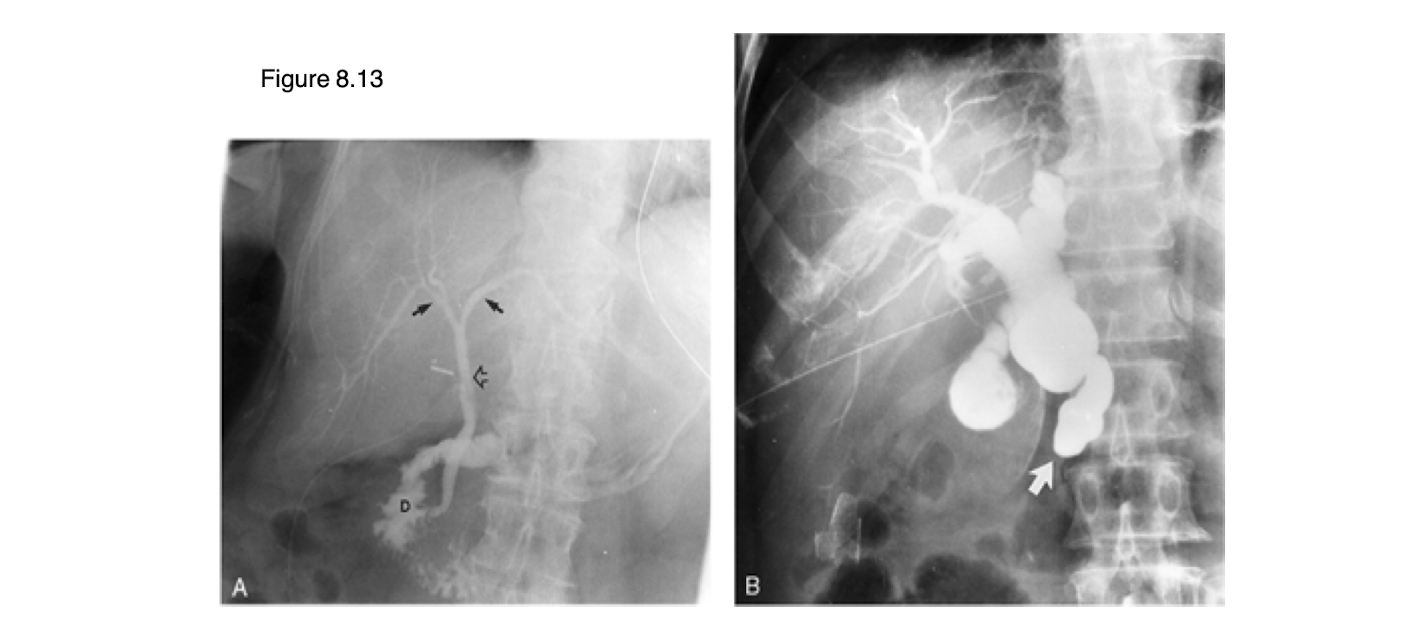

What are the images showing?

Duodenal ulcers